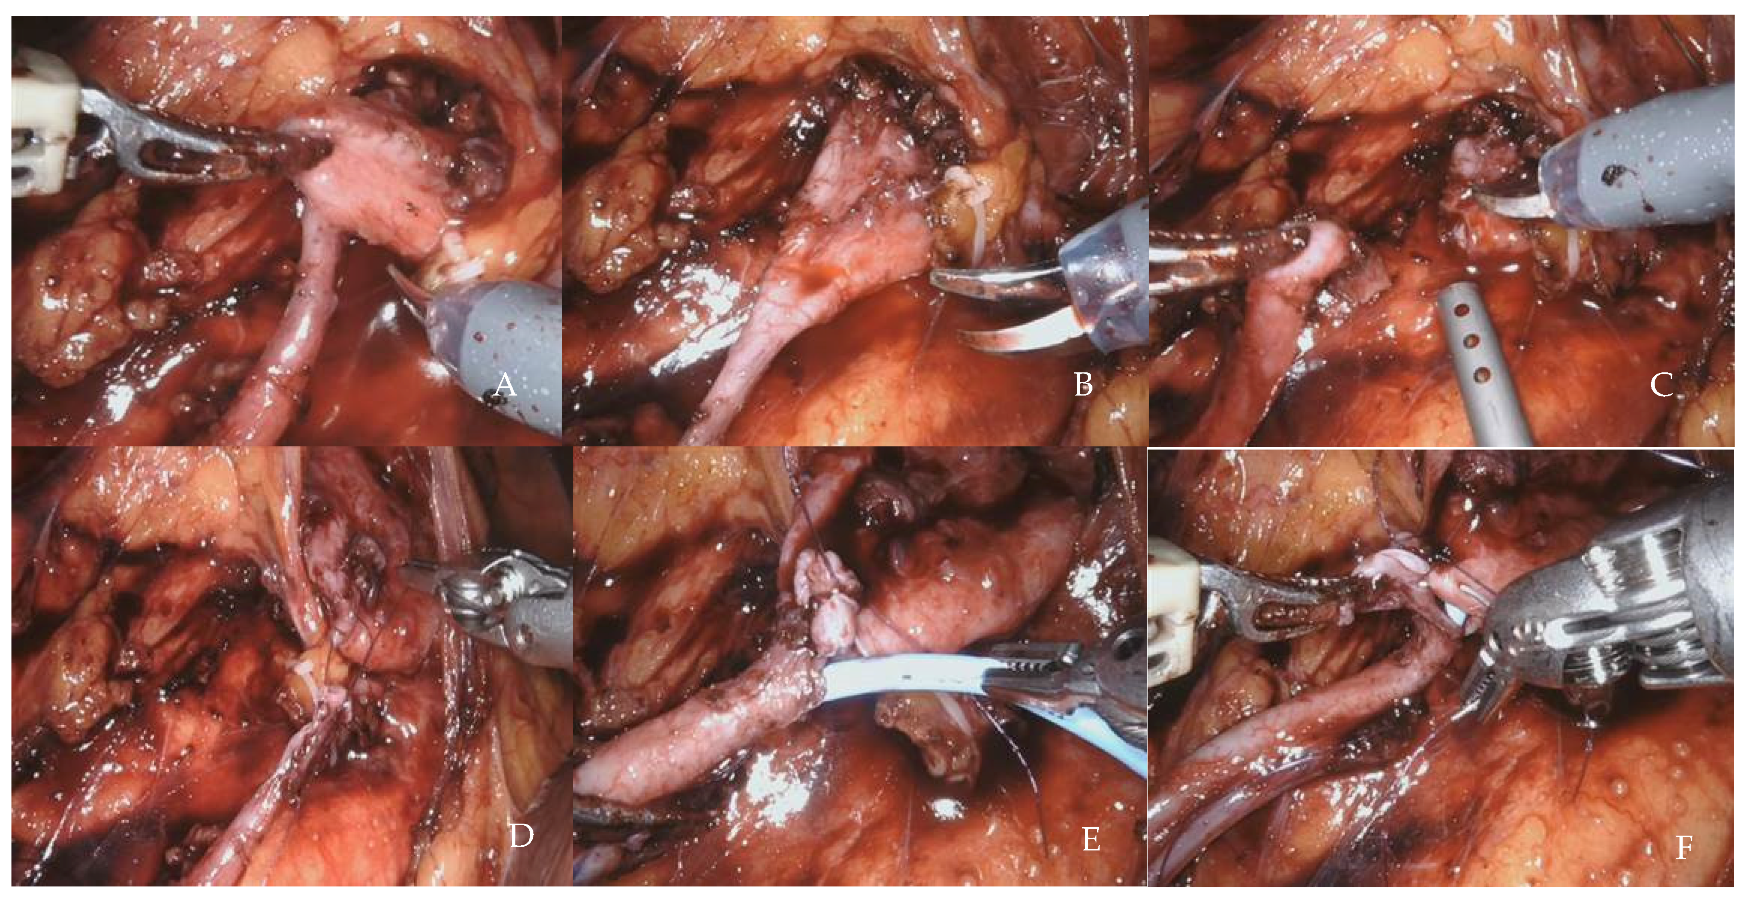

2.4.2. Robot-Assisted Laparoscopic Pyeloplasty

- Early preoperative removal (at least four weeks before) of a previously positioned stent, eventually replaced with a nephrostomy tube, to avoid inflamed tissues at the level of the UPJ.

- Limited isolation of the ureter and in situ anastomosis to avoid devascularization.

- Wide pelvis isolation to improve its mobilization.

- No coagulation on the ureteral and pelvis section margins.

- Landmark stitch on the ureter to avoid ureteral twisting.

- About 15 mm length of ureteral spatulation and pelvis opening, not including the scarred tissue that can be used for ureteral manipulation.

- Do not incorporate too much ureteral mucosa into the suture to avoid narrowing the anastomosis.

- Tension-free, watertight, and intubated anastomosis, usually performing a running suture, but an interrupted anastomosis, is a good alternative if there is too much tension.

- Kidney–psoas hitching if necessary to ensure a tension-free anastomosis, especially in the case of inflamed tissues (previous pyelonephritis, stone disease, or stenting).

- Avoid pelvis resection to shorten the suture length (pelvis tailoring is usually unnecessary).